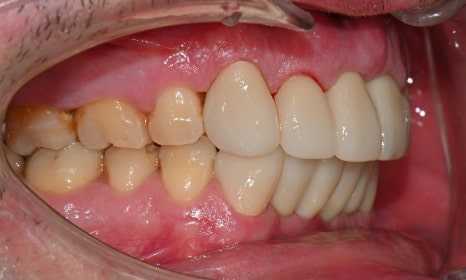

2026-1-7 최종 보철물 장착 : 연세정원치과

치료가 모두 마무리된 후, 환자분의 미소는 이전과 비교해 전반적으로 한층 더 안정적이고 조화로운 인상으로 개선되었습니다. 앞니의 길이, 형태, 배열이 아랫입술 곡선을 따라 형성되는 smile arc와 자연스럽게 조화를 이루면서, 웃을 때 과도한 긴장감 없이 부드러운 심미적 균형을 회복할 수 있었습니다. 기능적인 교합 안정성과 함께 심미적인 만족도 역시 높게 나타났으며, 환자분도 결과에 대해 매우 만족해하셨습니다.

앞니 심미보철은 단순히 치아 형태를 개선하는 치료가 아니라, 얼굴과 미소 전체의 조화를 고려해야 하는 치료입니다. 이번 증례에서는 진단 단계부터 임시 보철을 통한 검증, 최종 보철물 제작에 이르기까지 환자와의 충분한 소통을 바탕으로 디자인을 세밀하게 조정하였고, 그 결과 기능과 심미 모두에서 예측 가능하고 안정적인 결과로 치료를 마무리할 수 있었습니다. 환자 개개인의 조건과 니즈를 정확히 반영한 계획과 충분한 커뮤니케이션이 심미보철 치료에서 얼마나 중요한지를 다시 한번 확인할 수 있었던 케이스였습니다.